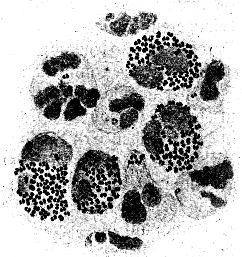

Sehr vieles sprach zugunsten der ersteren Anschauung; vor allem entsprach sie den Erfahrungen, die bei der Erforschung der lebenden Wesen unserer Erde bis dahin gesammelt waren. Der einwandfreie Nachweis ihrer Richtigkeit stieß aber auf eine sehr große Schwierigkeit: fast überall, wo wir in der Natur Bakterien in größeren Mengen begegnen, finden wir verschiedene, ja meist sogar sehr zahlreiche verschiedene Formen in buntem Durcheinander; z. B. treffen wir in einem Tröpfchen Zahnschleim regelmäßig kurze und lange, dünnere und dickere Stäbchen und Schrauben, daneben kleinere und größere[5] Kugelbakterien miteinander vermengt (vgl. Abb. 2). Es war so gut wie unmöglich, an solchen Bakteriengemischen einwandfreie Beobachtungen über die Fortpflanzungsweise der Bakterien zu machen. So ist es verständlich, daß über diese Frage die Ansichten lange Zeit auseinandergingen.

Bei einiger Übung werden wir aber bald erkennen, daß wir ein Kugelbakterium, ein Stäbchen- oder ein Schraubenbakterium vor uns haben. Mit wachsender Übung vermögen wir – unter Umständen auf den ersten Blick – besonders charakteristische Bakterienarten zu erkennen. Anderseits können wir bei sorgfältiger Beobachtung feine Unterschiede der Formen unter den Angehörigen der drei Grundtypen bald auffinden: so weichen z. B. manche Mikrokokken ein klein wenig von der Kugelgestalt ab, sie sind ein wenig abgeplattet; eine andere Art ist ein klein wenig längsoval, usf. Zur[13] Unterscheidung der Kugelbakterienarten, die im allgemeinen der Eigenbewegung ermangeln, kann uns auch die Art ihrer Lagebeziehungen im hängenden Tropfen wichtige Dienste leisten. Manche Arten bilden in einer Kultur regelmäßig perlschnurartige, kürzere oder längere, 3 bis 5, ja bis 30 und mehr einzelne Glieder aufweisende Ketten (Kettenkokken oder Streptokokken, vgl. Abb. 28, 29). Andere dagegen lagern sich zu weintraubenförmigen Häufchen zusammen und werden danach als Staphylokokken (ἡ σταφυλή die Weintraube) bezeichnet (vgl. Abb. 26). Zwischen den verschiedenen Arten der Stäbchen- und Schraubenbakterien bestehen ferner Unterschiede nach der Länge und Dicke und nach dem Verhältnis des Längen- zum Dickendurchmesser: so begegnen wir langen und schlanken, langen und plumpen, kurzen und schlanken, kurzen und plumpen Stäbchen- und Schraubenformen. Wenn wir sie genau betrachten, so können wir oft noch weitere feine Unterschiede zwischen den verschiedenen Arten erkennen: die einen besitzen abgerundete Enden, die anderen kantige, manche zeigen die Neigung, dadurch, daß mehrere Individuen aneinander haften, Fäden zu bilden, und so gibt es noch eine ganze Reihe feiner Gestaltmerkmale, die der sorgfältige Beobachter zu berücksichtigen hat.